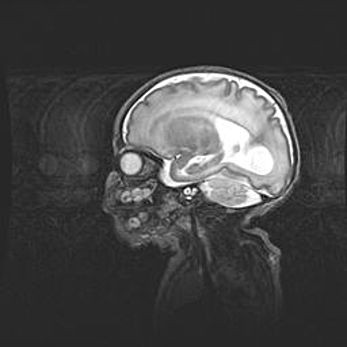

Подострая гематома правой гемисферы мозжечка.

Наружная гидроцефалия.

Возраст: 15 дней

Вес: 3100 г

Пол: женский

Окружность головы: 37 см

Срок гестации: 35-36 недель

При открытой наружной форме гидроцефалии у новорожденных расширяются и переполняются субарахноидные пространства.

Кровоизлияния в мозжечок имеют две клинико-анатомические формы: полушарные гематомы и кровоизлияния в червь.

К появлению этой патологии может привести: повреждения головного мозга, возникающие в результате асфиксии и гипоксии плода при беременности, или травмы во время родов. Редко гематома мозжечка может быть результатом первичной коагулопатии и сосудистой мальформации, диссеминированном внутрисосудистом свертывании, изоиммунной тромбоцитопении.